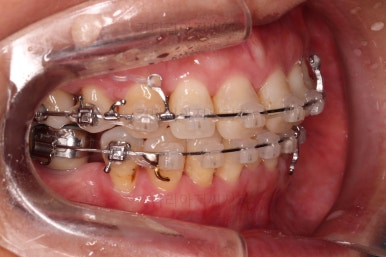

작은 어금니를 발치하고 치열을 가지런하게 해줍니다.

아직 아래 앞니에 있는 유치는 발치하지 않았는데요.

현 상태로 발치를 하게 되면 기구 접근이 되지 않아 광범위하게 뼈를 갈아내며 뽑아야 됩니다.

교정을 하면 기구 접근이 충분히 되도록 공간을 벌린 뒤 발치를 할 수 있어 기간은 더 걸릴 수 있겠지만 잇몸뼈를 보존하고 수월하게 발치를 하려면 교정만한게 또 없죠.

적절한 시점에 유치를 뽑아내고 남은 공간을 줄여나갑니다.

아래쪽 임플란트는 움직이지 않기 때문에 해당 치아를 기준으로 다른 치아를 모두 셋팅해야 하는 매우 난이도 높은 치료가 진행되었습니다.